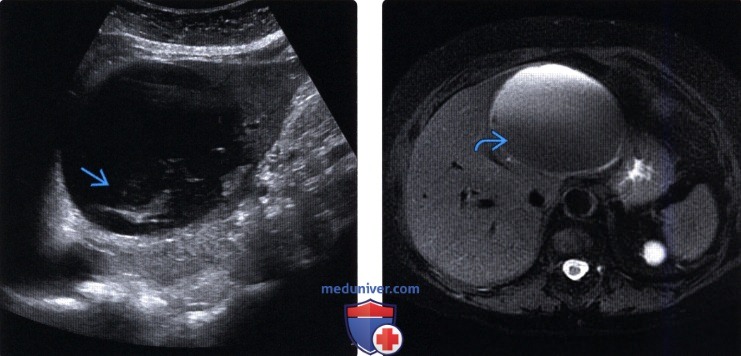

Компьютерная томография в диагностике печеночных кист, по мнению некоторых авторов, превосходит ультрасонографию [Люлинский О.М. и др., 1990]. Метод позволяет более четко визуализировать структуру кисты и выявляет печеночные кисты до 0,5 см в диаметре. Специфичность исследования высока и колеблется от 91 до 99% [Мовчун А.А. и др., 1989]. Важнейший критерий при дифференциальной диагностике очаговых образований печени — их денситометрические показатели. При кистах печени их величина колеблется от 5 до 20 единиц.

На компьютерных томограммах кисты печени определяются в виде гомогенных полостей с четкими ровными контурами. В полости непаразитарных кист могут встречаться плотные включения, негомогенные, плотность которых составляет до 20-30 единиц. Плотность непаразитарных кист ниже плотности эхинококковых кист печени. Сложности возникают на ранних стадиях развития паразита, когда денситометрические показатели при той и другой патологии одинаковы.

В некоторых случаях при компьютерной томографии молодые эхинококковые кисты неотличимы от непаразитарных [Вилявин М.Ю., 1986]. При компьютерной томографии у 65% больных эхинококкозом в полости кист обнаруживаются дочерние пузыри.

При наличии болезней печени и желчных путей МРТ покажет нарушения в их структуре. При циррозе орган увеличен либо уменьшен в размерах, с бугристыми контурами, расширенными сосудами системы воротной вены. Киста выглядит как округлое образование относительно правильной формы, заполненное жидкостью, не поглощающей контраст. Паразитарные кисты дополнительно содержат в полости перегородки и камеры.